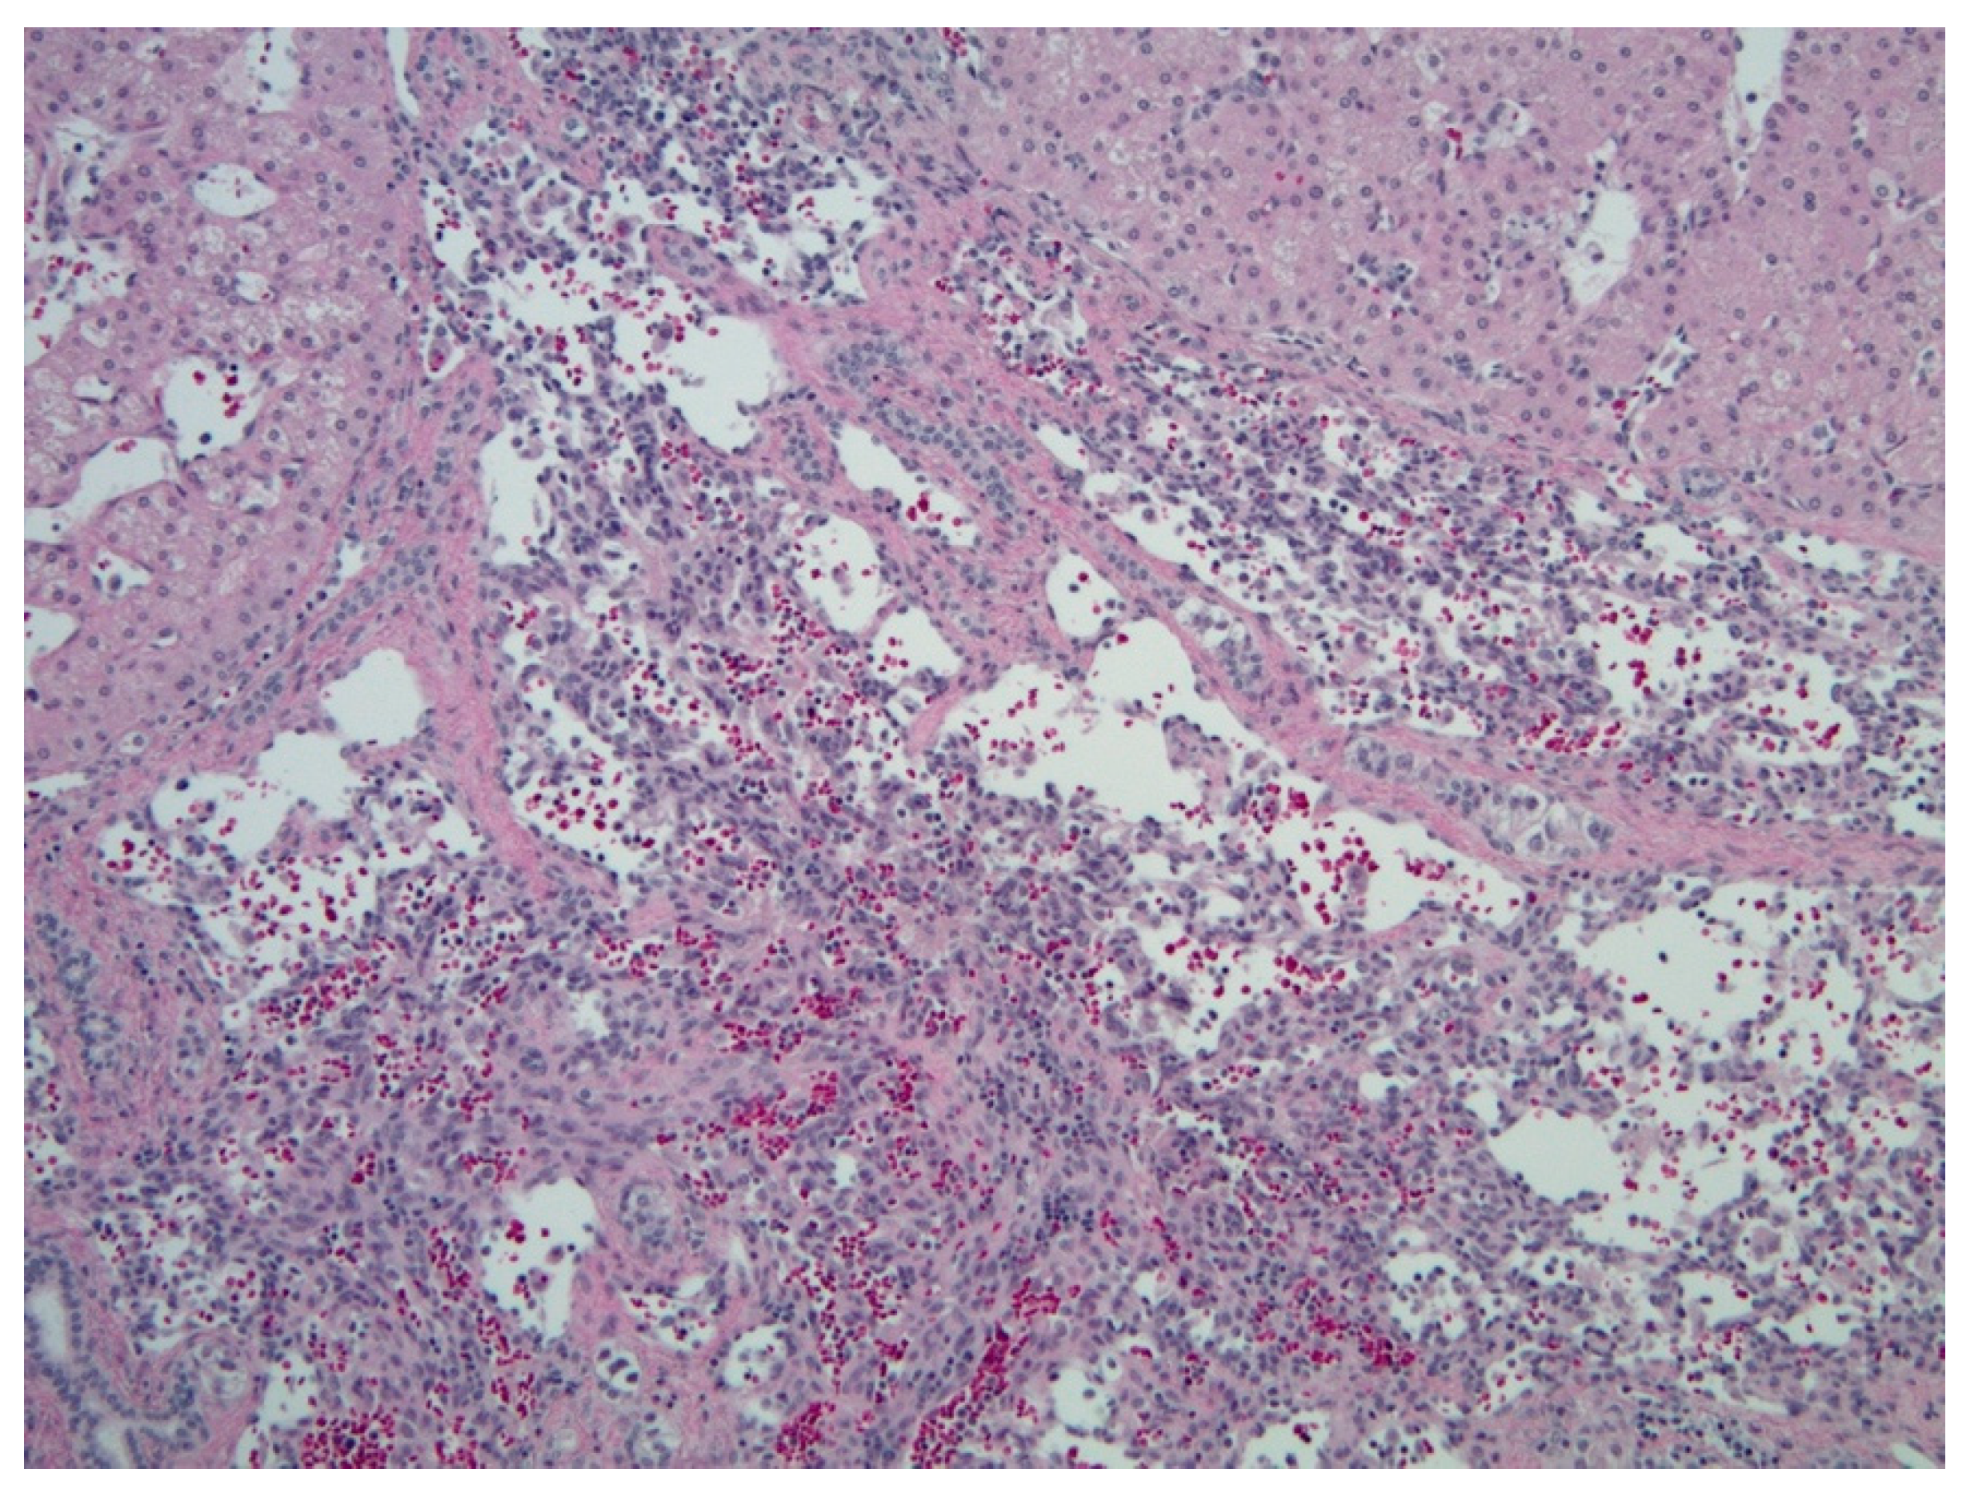

5.2.5. Histopathology and Immunohistochemistry